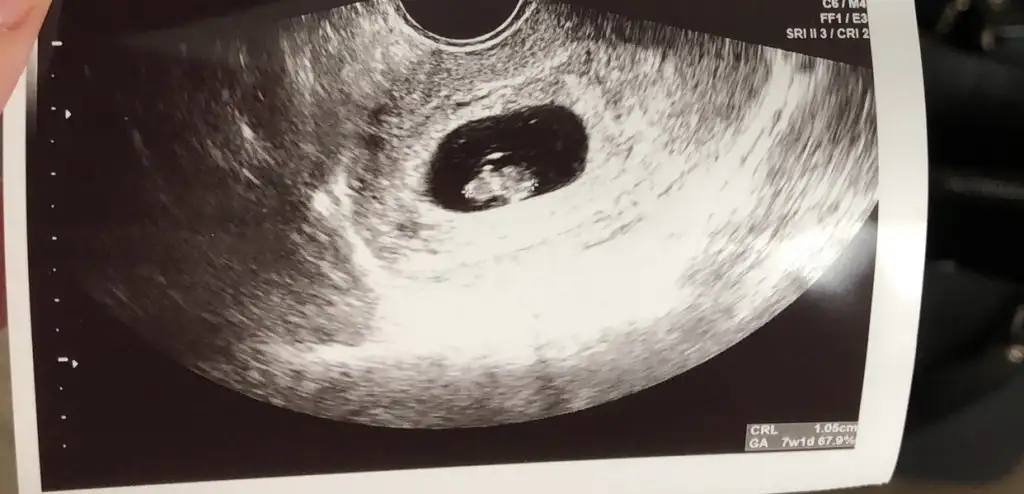

Banada yorum yaparmısınız 7+1 alttan muane ile bakıldı kalp atıslarını duydumuz gün. Hiç farketmiyor cinsiyeti ama ramzi diye bişey duydum 🤗